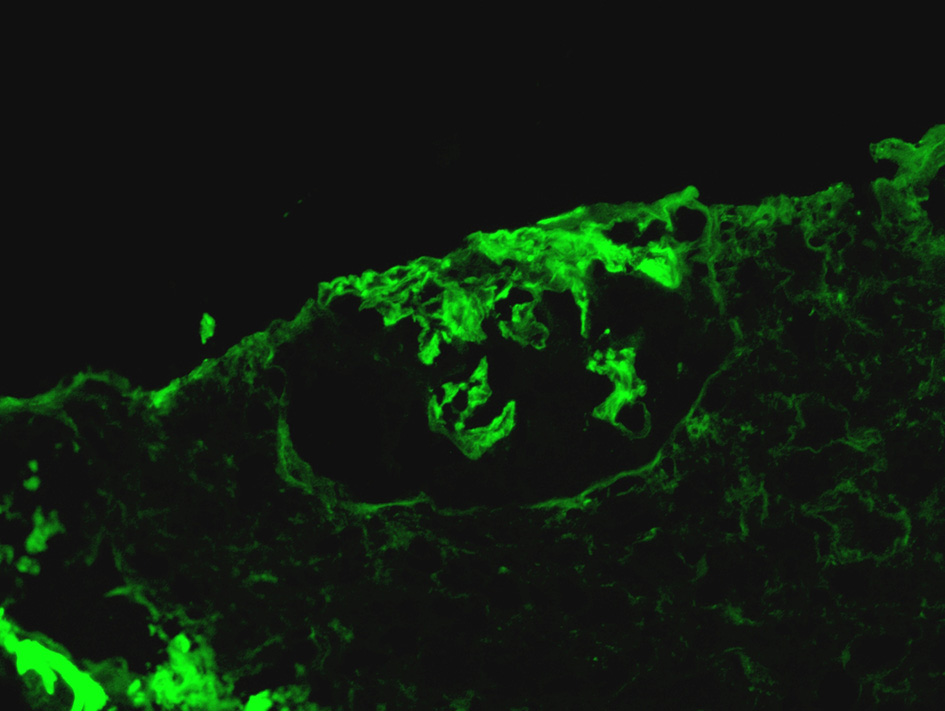

Immunofluorescence microscopy demonstrated linear (2+) staining along the glomerular capillary loops for IgG (Figure 1) supported the diagnosis of anti-GBM disease. Half of 5 glomeruli also showed 2+ patchy staining for C3. In addition, 1-2 + patchy mesangial staining for IgM was also noted. There was no evidence of IgA, Kappa, lambda, and C4 or C1q deposition.

Figure 1

Linear (2+) staining along the glomerular capillary loops for IgG.